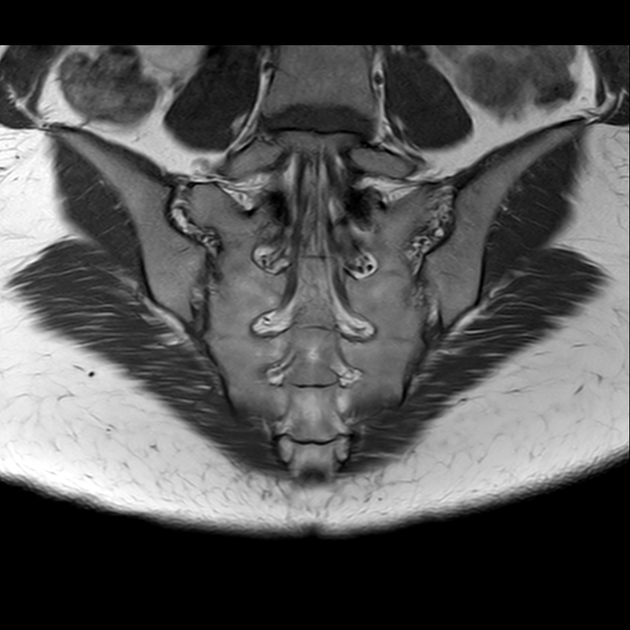

磁共振检查:

T2

磁共振影像表现